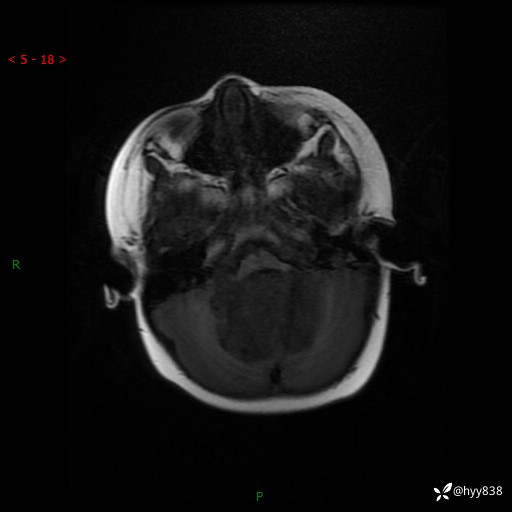

颅脑CT平扫

颅脑MRI平扫+增强